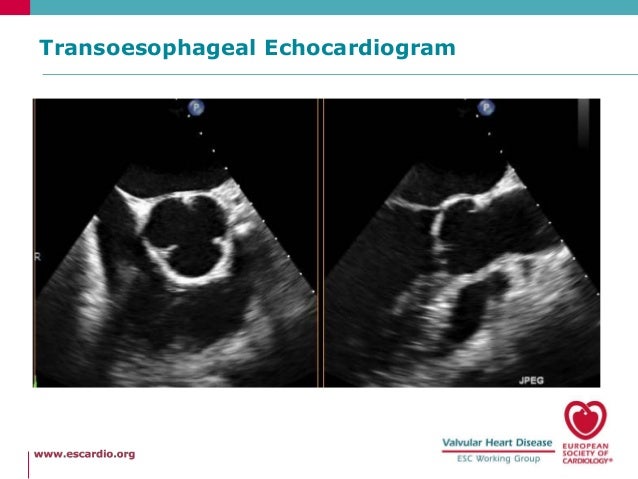

The development and timing of aortic valve prolapse (AoVP) and aortic regurgitation (AR) was studied by two-dimensional echocardiography in 99 consecutive patients with supracristal ventricular septal defect (VSD). Thirty patients (30%) had aortic valve prolapse (VSD + AoVP group), and 31 patients (31%) had AoVP with AR (VSD + AoVP + AR group). In the VSD + AoVP group, AoVP was detected first by echocardiography at the age of 6.8 +/- 4.2 years (mean +/- SD). In the VSD + AoVP + AR group, the interval from detection of AoVP to the appearance of AR was 3.4 +/- 2.0 years. The configuration of the prolapsed aortic valve was echocardiographically classified into two types: tear-drop type (small) prolapse and box type (large) prolapse. The frequency of tear-drop type prolapse was not significantly different between VSD + AoVP and VSD + AoVP + AR groups (43% versus 32%, respectively), indicating that even minor AoVP can result in AR. Four infants (4%) had AoVP at the ages of 1, 5, 7, and 11 months, respectively. All infants had tear-drop type prolapse. Two infants developed AR by colour flow mapping at the ages of 3 and 11 months, and the interval from prolapse to AR was only 2 and 4 months, respectively.

Aortic valce involvement can develop under the age of 1 year in supracristal VSD. Regular evaluation by two-dimensional echocardiography with colour flow mapping is important in the follow-up of children with supracristal VSD.